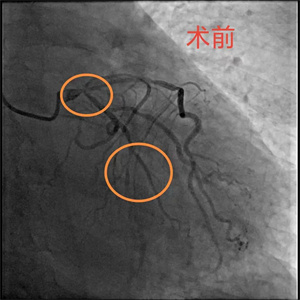

患者,李大爷(化名),76岁,因突发胸痛被家属送至我院急诊科,经完善心电图等检查后,被诊断为急性心肌梗死,随后,病人迅速被送至导管室。完善冠脉造影检查后,患者血管显影结果不容乐观,考虑左主干真性分叉合并三支病变,即右冠慢性闭塞、回旋支急性闭塞、前降支严重狭窄伴钙化。与此同时,患者出现血压、氧饱和度下降的情况,病情极其危重,随时面临死亡风险,已无法耐受及等待外科搭桥手术,急需急诊介入治疗。

关键时刻,心血管内科副主任医师吴义权、主治医师孙春根、夏秋旺和介入团队紧密协作,在IABP的保护下快速开通血管。术后,患者转入心血管内科监护病房。在医护团队的精心医治和悉心照料下,现已平安出院。